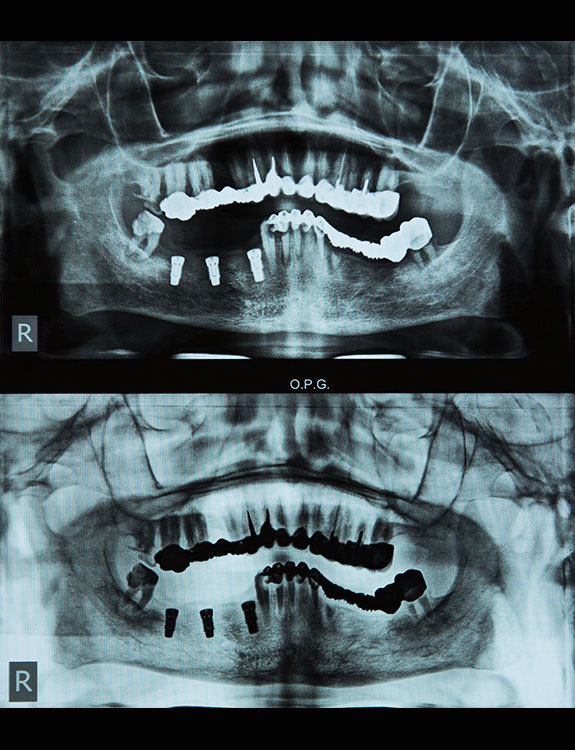

Missing teeth can affect not just your smile, but also your confidence, chewing ability, and overall oral health. At Dental Que, we offer advanced Dental Implants in Punjabi Bagh, West Delhi, designed to restore the look, feel, and function of natural teeth with long-lasting results.

Dental implants are artificial tooth roots made of medical-grade titanium that are surgically placed into the jawbone. Once the implant integrates with the bone, a crown is fixed on top, giving you a strong, natural-looking replacement tooth.

If you are searching for reliable Dental Implants in Punjabi Bagh, Dental Que provides personalized solutions based on your oral health, bone condition, and smile goals.